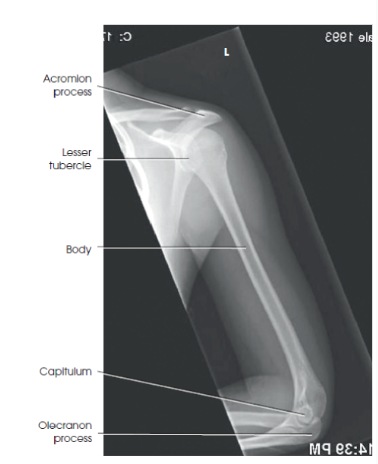

What are the structures shown/evaluation criteria for an AP humerus?

hints

Joints

rotation?

what should be in profile

lesser tubercle?

A

Elbow and shoulder joints should be seen

humeral epicondyles without rotation

humeral head and greater tubercle in profile

outline of lesser tubercle, located between humeral head and greater tubercle